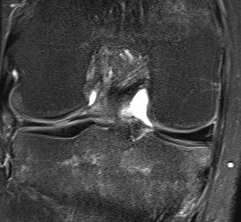

Signs of bucket handle tear meniscus

1. Double PCL sign

- medial Meniscus

2. Absent bow tie sign

- should see bow tie image on 2 consecutive sagittal slices of 5 mm

3. Fragment in notch sign

4. Anterior flipped meniscal sign

- torn fragment flips over the anterior horn of the affected meniscus

5. Truncated meniscus